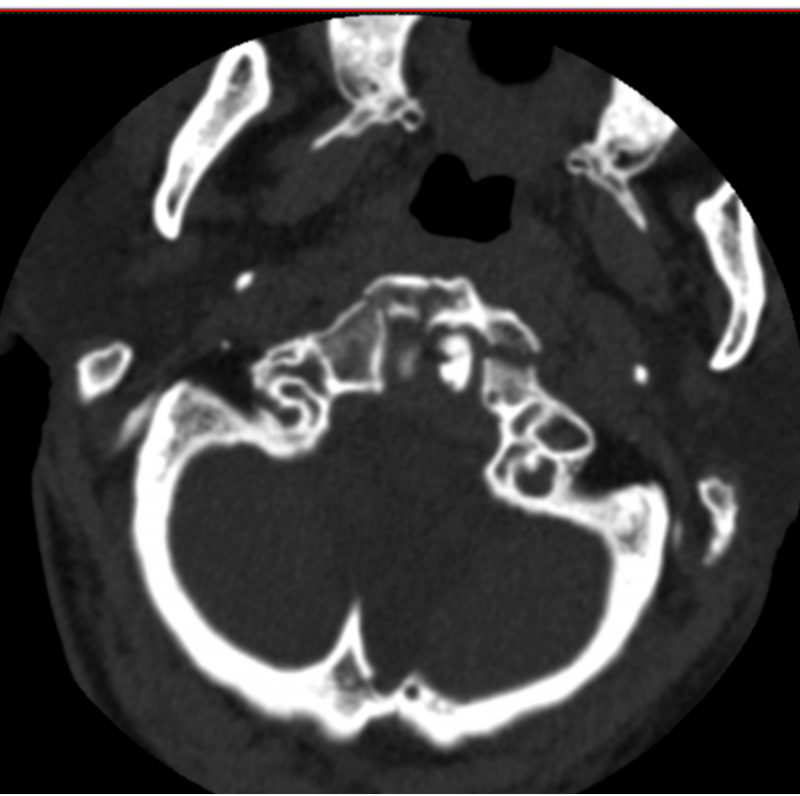

73歲的黃先生因不慎摔倒從山坡上滾下頭面部先著地致“寰椎骨折”入住惠州市中心人民醫(yī)院博羅分院(博羅縣人民醫(yī)院)脊柱外科。入院時(shí)患者頸肩部、雙上臂疼痛劇烈,伴有雙上肢麻木感,活動(dòng)受限。

術(shù)前檢查

初期給予黃先生頸托外固定保守治療,但考慮頸托限制活動(dòng)不穩(wěn)定,容易松動(dòng),上頸椎解剖位置關(guān)系特殊,位置重要,且鄰近解剖關(guān)系復(fù)雜,病變引起的臨床癥狀嚴(yán)重、多變及輕重不一,愈合率低,其中老年患者保守治療的死亡率高達(dá)21%-33.3%,是年輕患者的21倍,而該骨折手術(shù)風(fēng)險(xiǎn)大、技術(shù)難度高,患者及家屬對(duì)手術(shù)心存顧慮。面對(duì)此困境,姚仕奮主任憑借豐富的臨床經(jīng)驗(yàn),深入分析了患者的病情及身體狀況,經(jīng)過多次科室討論,建議黃先生進(jìn)行寰椎骨折閉合復(fù)位halo架外固定術(shù)治療,halo架無需手術(shù),避免上頸椎手術(shù)的高風(fēng)險(xiǎn),且能提供穩(wěn)定的頸椎外固定,治療效果確切,并且避免患者長期臥床而導(dǎo)致各種并發(fā)癥。

姚仕奮表示,黃先生的寰椎骨折屬于高位頸椎損傷,不幸中的萬幸是受傷后頸椎骨折后釋放了大部分暴力,雖然寰椎前弓粉碎性骨折比較嚴(yán)重,但頸椎脊髓反而受傷較輕,經(jīng)過及時(shí)恰當(dāng)治療,預(yù)后恢復(fù)良好。因此,他提醒,廣大市民們要引起高度重視,對(duì)于脊柱骨折脊髓損傷患者應(yīng)及時(shí)就近診治,特別是頸椎受傷后肢體麻木乏力者不要隨意移動(dòng),需及時(shí)送到有脊柱外科專業(yè)團(tuán)隊(duì)的醫(yī)院救治,曾出現(xiàn)過病人傷后不恰當(dāng)搬運(yùn)及轉(zhuǎn)運(yùn)而出現(xiàn)癥狀加重的情況,甚是可惜。